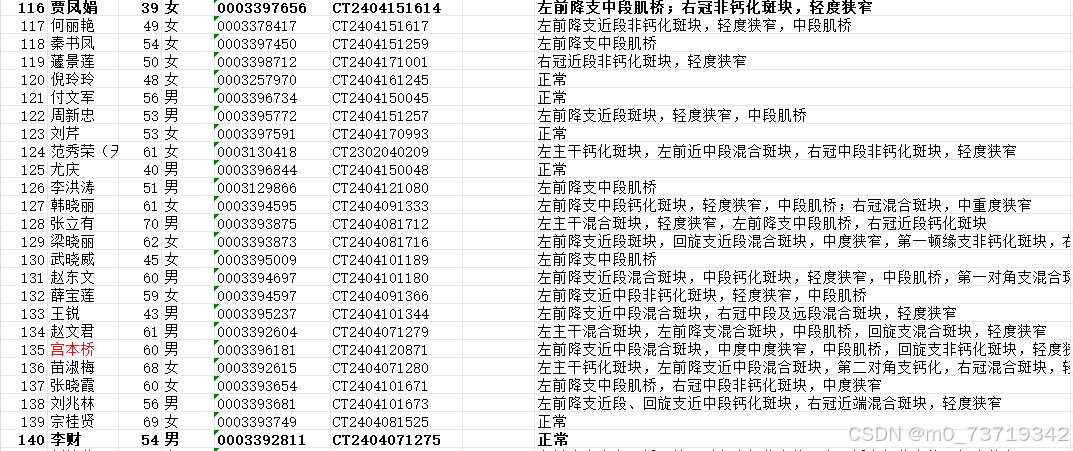

方法一:二维图像观察

钙化板块特点:高亮(对比度高于血管)如图所示

非钙化斑块特点:暗沉(对比度低于血管)如图所示